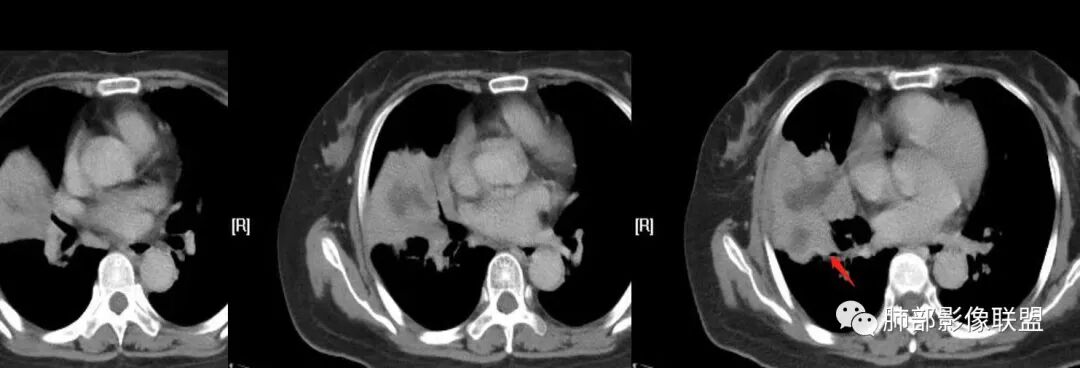

慢性咳嗽,抗炎复查无好转,原右肺中叶实边,外侧段支气管开口阻断,复查无好转,逐渐向下叶外前基底段融合形成大肿块,边缘膨隆,密度不均匀,坏死轮廓不清,内血管束破坏,累及中轴间质厚,外围分布,方向恶性,与炎性肉芽肿鉴别,隐球荚膜抗原先排查!

女,74岁,咳嗽咳痰加重一周入院,右肺中叶大片实变影,边界清晰,病灶内密度不均匀,右肺中叶支气管变窄,增强扫描病灶明显强化,考虑恶性病变能,鉴别肺脓肿。

右肺中叶实变,支气管开口阻断,边缘膨隆,密度不均匀,坏死边界清晰,胸膜累及,。一般抗感染治疗无效。考虑恶性。

老年女性患者,慢性病程,两次活检均提示炎性病变,胸部CT:右肺中叶大片实变密度影,边界尚清楚,部分收缩,部分膨隆,内部有低密度坏死,坏死边界清楚,无明显结节感,无分割,总体考虑炎性病变,机化性肺炎,NTM,慢性肺脓肿,鉴别:恶性,腺癌

右肺中叶大片实变,内见大片的坏死,中叶外侧段支气管阻塞,相邻胸膜增厚,间隔约四个月后复查,发现低密度坏死内可见气泡影,老年人,反复迁延不愈的病变要考虑恶性,首先考虑腺癌伴感染。鉴别慢性脓肿。

右肺胸膜下实变,跨叶,形态不规则,局部边缘膨隆,中叶支气管外侧段进入后阻塞伴不张,不均匀强化,其内坏死边界欠清晰,复查无吸收,考虑腺癌,鉴别慢性炎症伴脓肿

右肺大片状高密度灶,跨叶,密度不均,边缘膨隆,支气管阻塞,粘液栓,不均匀强化,其内坏死边界欠清晰,复查无吸收,考虑腺癌,鉴别慢性炎症,脓肿

胸部CT:右肺中下叶大片实变影,界清,边缘膨隆为主,中叶外侧段支气管截断。增强不均匀强化,边缘可见血管影迂曲模糊,内见条带状低密度影。治疗后病变进展。考虑恶性,鳞Ca?鉴别TB、OP。

老年女性,慢性病史,炎性指标稍高,肿标正常,右中下肺大片实变,跨叶生长,边界清,收缩力差,膨隆生长为主,支气管杵状截断,均匀强化,其内坏死边界清,可见悬浮气泡,整体观察,病灶膨隆生长为主,邻近肺野无播散灶,形态单一,尽管慢性病史,影像不支持OP和TB,支气管截断呈杵状,肿标正常,均匀强化,虽是高龄患者,诊断恶性肿瘤有点牵强,综和分析,首选炎性病变放线菌感染,其次考虑低度恶性占位炎机母。